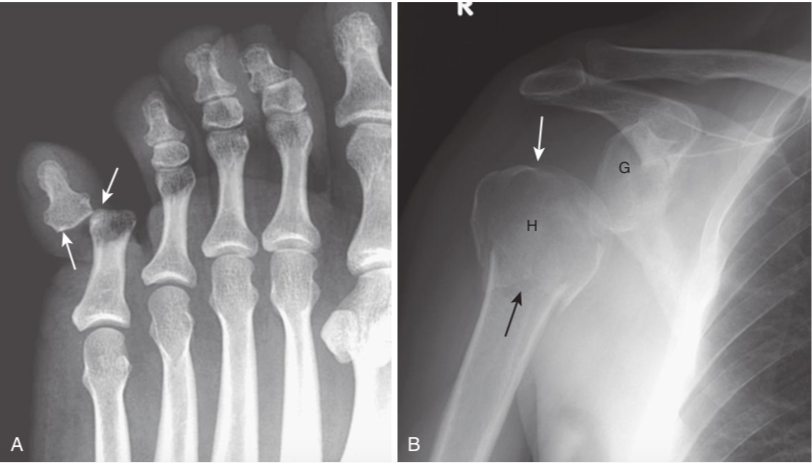

Pitfalls in fracture diagnosis.

A,Old, unhealed fracture fragments (whitearrow). B,Sesamoids (bones that form in a tendon as it passes over a joint) (whitearrows). C,Accessory ossicles (acces- sory epiphyseal or apophyseal ossification centers that do not fuse with the parent bone, such as this os trigonum;white arrow). These examples can sometimes mimic acute fractures. Unlike fractures, these small bones are corticated (i.e., there is a white line that completely surrounds the bony fragment), and their edges are usually smooth. Sesamoids and accessory ossicles are usually bilaterally symmetrical.

Dislocation and subluxation.

A,In a dislocation, the bones that originally formed the two components of the interphalangeal joint are no longer in apposition to each other (white arrows). The terminal phalanx is dislocated laterally. B,In a subluxation, the bones that originally formed the two components of a joint are in partial contact with each other. The humeral head (H) is subluxed inferiorly (white arrow)in the glenoid (G) because of a large hematoma in the joint secondary to a fracture of the surgical neck of the humerus (black arrow). The hematoma itself is not visible by conventional radiography.